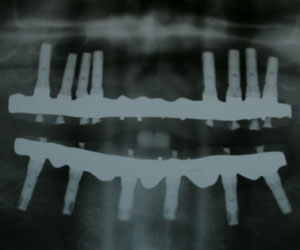

![Radiographie - 2 bridges complets sur implants]()

2 bridges complets sur implants

Il vous manque toutes les dents

Vous souhaitez limiter l’inconfort de la prothèse complète mobile ? Deux implants à la mâchoire du bas pourront créer une rétention secondaire. Certes, vous restez en prothèse amovible, mais elle est stabilisée. Il s’agit du traitement minimal recommandé par un consensus médical de 2001 en cas d’édentement complet.

Vous pouvez bien entendu opter pour la réalisation d’un bridge ostéo-ancré fixe. Vous pouvez ainsi vous voir parler, chanter, rire, mâcher, éternuer sans que votre prothèse dentaire ne risque de se détacher. Vous avez choisi de la visser sur 4 implants au minimum.